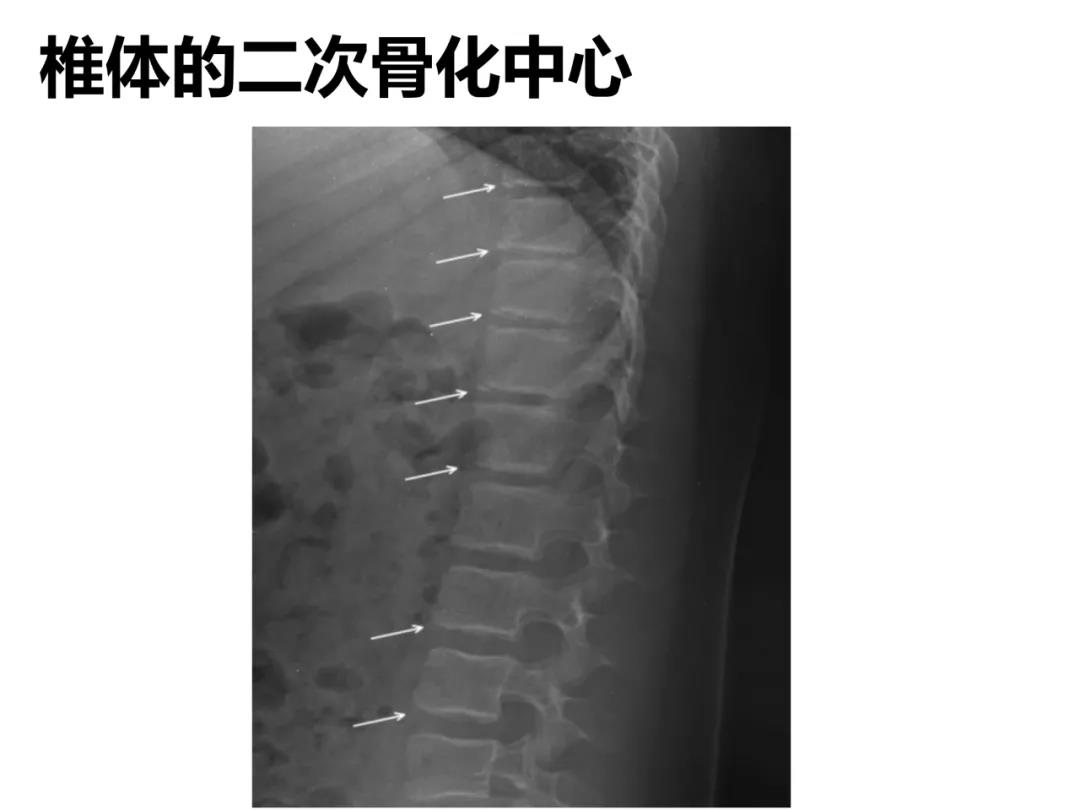

小儿骨科X线片汇总,临床读片宝典!